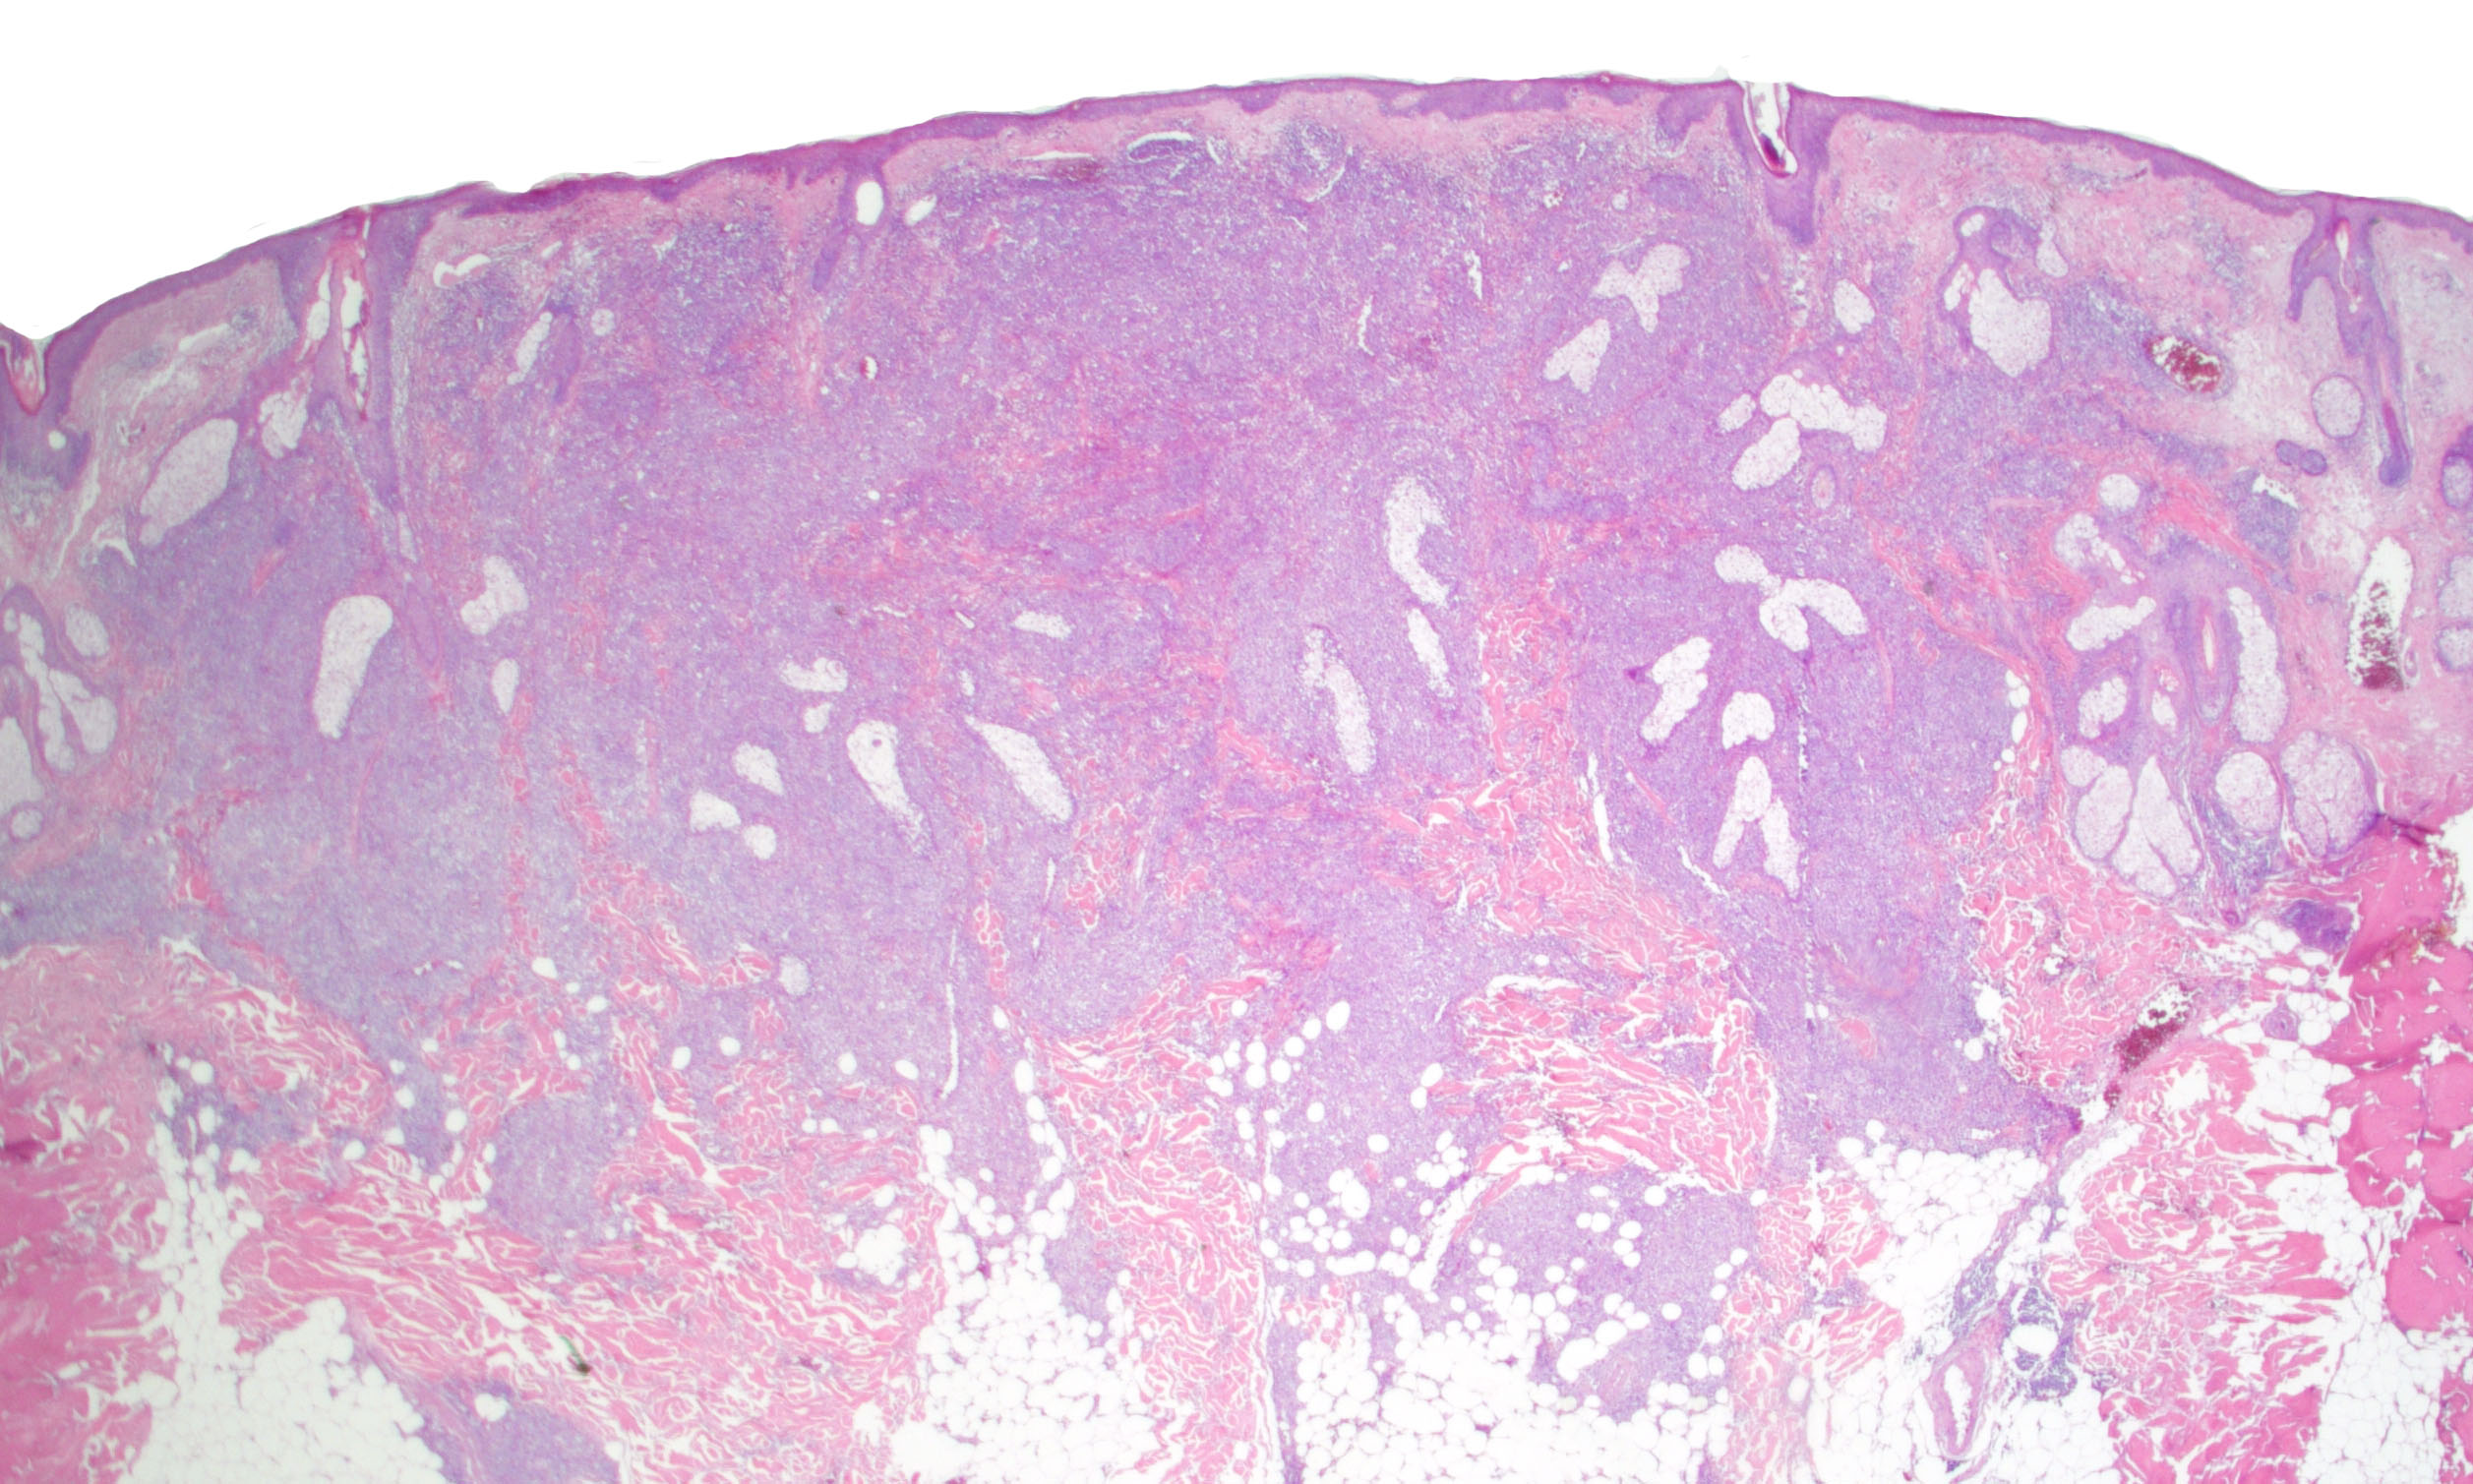

- Lymphomatoid papulosis is characterized by a wedge shaped pattern, with a wide superficial base and the tip at the bottom, usually deep dermis and less frequently into the subcutaneous tissue

- The most characteristic appearance is the presence of few to numerous large cells with a Hodgkin or Hodgkin-Reed Sternberg admixed with a reactive background of small lymphocytes and less frequently eosinophils, plasma cells and histiocytes

- Type A: wedge shaped and extensive lymphoid infiltrate with neutrophils, eosinophils and histiocytes; CD30+ cells are scattered and the overall histologic appearance mimics classic Hodgkin lymphoma

Microscopic (histologic) images

Contributed by Roberto N. Miranda, M.D.